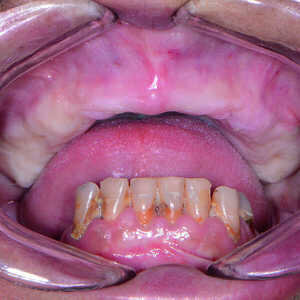

Une patiente dans la cinquantaine a consulté mon cabinet pour le traitement de son maxillaire édenté et de ses dents mandibulaires extrêmement déchaussées et cariées (Figs. 1 et 2). La patiente était une grande fumeuse, n’avait consulté aucun dentiste depuis plusieurs années, et négligeait de prendre soin de ses dents restantes en raison de l’inconfort et de la douleur qu’elle ressentait.

Fig-1-Vue-préopératoire-avec-écarteur-de-lèvres-300x300-

Fig-2-Vue-préopératoire-avec-écarteur-de-lèvres-sans-prothèse-300x300-